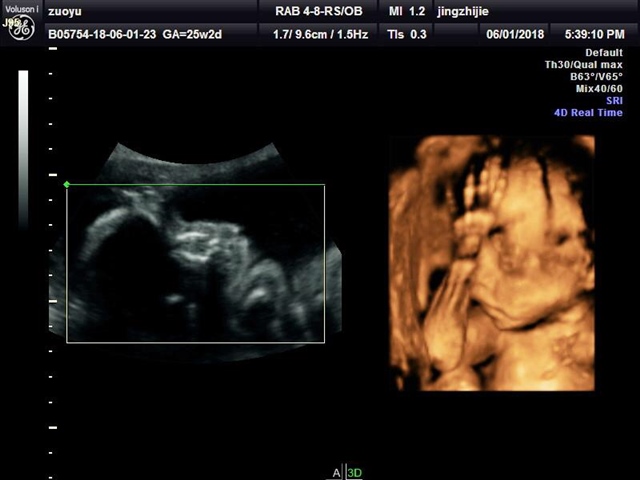

孕22周+3天

张嘴打哈欠那张萌到我了😄

叮噹猫[帖主]:哈哈……我们这边医院每次B超我们什么都看不到,我特意去的外面摄影工作室拍的四维,6个多月以来第一次见到宝宝的影像,打哈欠刚好拍成视频了,第一个六一节还纪念了一下